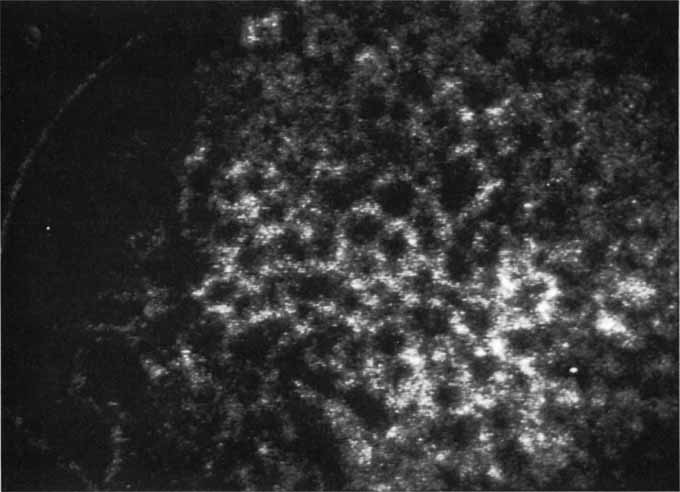

Most promising in this category of inflammatory choroidopathies is a better detection and understanding of the lesions of multifocal choroiditis. Multiple large, scattered, hypofluorescent spots are seen on ICG angiography, particularly in the later phases of the angiogram69 (Fig. 18). These lesions are not evident either on clinical examination or on fluorescein angiography. In addition to having these larger hypofluorescent lesions, patients with multifocal choroiditis have smaller dot-like lesions and hyperfluorescent foci that do not correlate with lesions seen clinically or by FA. They involve the posterior pole and in some patients extend into the mid-periphery. There is also a “papillotropic” involvement, with confluent hypofluorescent lesions surrounding the optic nerve,69 which may be useful in understanding the associated blind-spot enlargement evident in this condition.70 Other zonal visual field defects have been associated with this condition,70 and corresponding ICG abnormalities have been documented in some patients.69

Fig. 18 A. Clinical photograph of a patient with active inflammation associated with multifocal choroiditis. An atrophic scar from previous laser photocoagulation treatment is noted in the temporal macula. The patient reported visual disturbance, and an enlarged blind spot was noted on visual field testing. B. Late-phase indocyanine green study demonstrating a multitude of hypofluorescent spots that were larger than those seen with multiple evanescent white dot syndrome and more numerous and more extensively distributed than appreciated on clinical examination. Note that there is marked confluence of these lesions around the optic nerve, which may help to explain the enlarged blind spot noted on visual field testing.